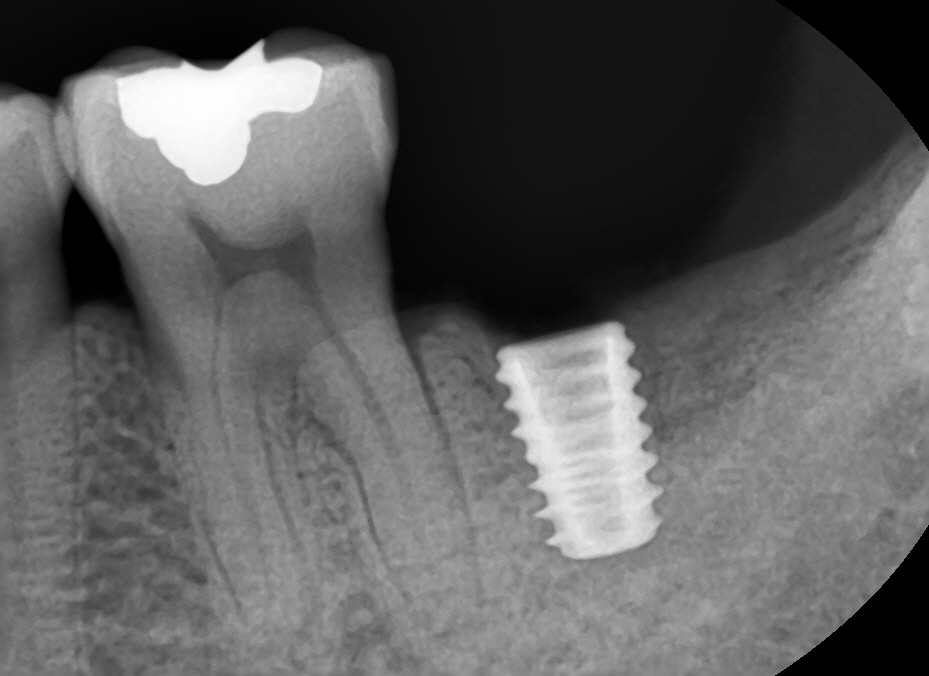

전에 여성환자분께는 4.5파이 드릴링하고 4.5파이 수월하게 심었는데 이번엔 5.0드릴링 하고 5.0심는데도 빡빡하게 들어갔다. 5.5드릴을 절반정도만 담궈서 코로날부위만이라도 좀 쉐이핑을 하고 했으면 훨씬 나았을텐데 막상 지금 단계에 정신이 팔리니 배운것도 잘 못써먹더라. 픽스쳐가 빡빡하게 들어가니 환자분께서도 좀 불편해하셨다.

방향은 만족스러웠고 다만 픽스쳐 길이와 깊이에 아쉬움이 좀 남는다. 36distal bone에 스타퍼가 걸리는 문제 때문에 총 1시간이 넘게 걸렸고 환자분께서 아파하셔서 드릴링을 또 한번 하기가 내 마음이 아파서 픽스쳐 길이 안바꾸고 5mm 힐링 달고 마무리 했다. 사실 중간에 4.5 심었는데 7mm힐링 달았더니 김영삼원장님께서 보시곤 7mm빼고 5mm로 하라고 하셔서, 7mm힐링 풀다가 (조일 때 너무 꽉 쪼여놔서)픽스쳐도 같이 빠지긴 했는데~ 그 덕에 4.5에서 5.0으로 쉽게 바꿨다ㅋㅋ;; 한단계 덜어줬다..ㅋㅋㅋ...ㅋㅋ🤣